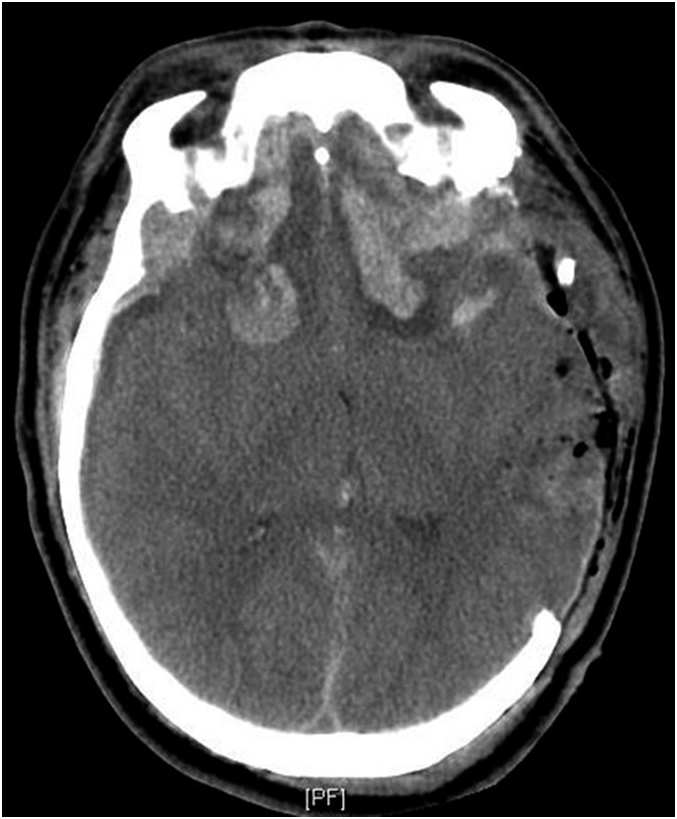

Intracerebral Hemorrhage After Intravenous t-PA Therapy for Ischemic Stroke